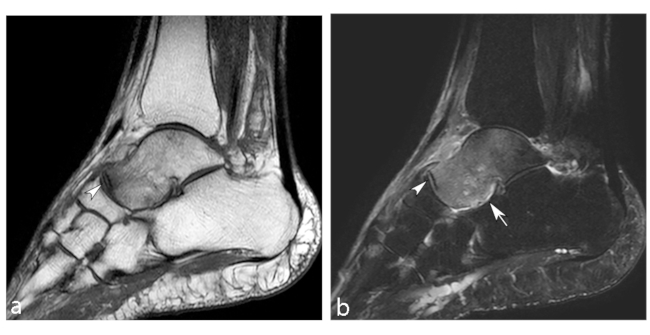

El astrágalo es el segundo hueso más grande del tarso y presenta una estructura que permite distribuir el peso corporal. La ausencia de inserciones musculares y escasas ligamentosas en este hueso hace que la vascularización extraósea sea menor que en otros huesos. Además, el 60% de su superficie presenta cartílago articular, con ausencia a nivel del cuello y parte posterior del cuerpo.16 Dentro del hueso, los territorios vasculares son autónomos, la cabeza y el cuello están bien vascularizados por ramas que penetran por la parte superior o inferior del cuello. Por el contrario, el cuerpo presenta una vascularización bastante pobre.17,18

La ON del astrágalo guarda una estrecha relación con los traumatismos; la necrosis atraumática solo representa un 10% de los casos.6,16 Existen dos lesiones traumáticas que potencialmente pueden desencadenar la aparición de la ON: fracturas del cuello del astrágalo y dislocación del astrágalo.17

Aunque no existe un sistema de clasificación específica, la ON del astrágalo exhibe un patrón característico de la enfermedad. Por lo general, aparece como un área de esclerosis en la cúpula del astrágalo que puede extenderse en el cuerpo talar, con posible colapso de la superficie articular y, en casos graves, la fragmentación de la cúpula del astrágalo y el cuerpo.

La RM es la técnica más sensible, especialmente en las primeras etapas, siendo de mayor ayuda diagnóstica cuando hay una alta sospecha clínica de NOA y los hallazgos radiográficos son normales (►Fig. 8).6,16